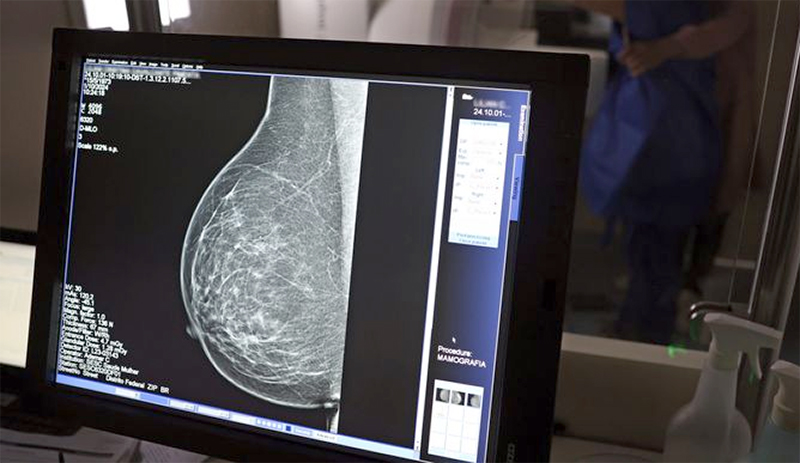

Laboratórios de Microbiologia e Hematologia, Mamografia e Raio X do

HRAN - Hospital Regional da Asa Norte © Rodrigo Nunes/MS

Um dos principais critérios é a realização de rastreamento organizado, ou seja, a convocação das usuárias para realizarem exames regularmente, mesmo sem sintomas. No caso do câncer de mama, a cartilha seguiu o protocolo do Ministério da Saúde e do Instituto Nacional do Câncer (Inca): mamografias a cada dois anos para as mulheres com idades entre 50 e 69 anos.

Para as entidades médicas, a mamografia deve incluir essas pessoas, porque o diagnóstico de câncer em pessoas assintomáticas, a partir de exames de imagem, demanda tratamentos que impactam menos a qualidade de vida da paciente, e tem menos risco de recidivas, metástases e mortalidade.